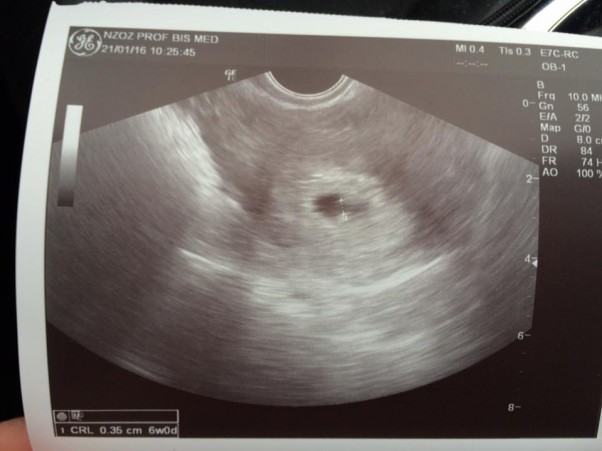

Jedyny plus to taki ze 3 dni temu nie było pęcherzyka żółtkowego teraz jest czyli coś się rozwija za to z owalnego zrobił się nieregularny... Wiem że jeszcze piłka w grze ale nie ukrywam że się boje

Smutnamiss wrote:Dziewczyny ja zwariuje pęcherzyk jest w macicy. Opis usg pojedynczy pęcherzyk z zatartym echem zarodka fhr nieuwidoczniono niewielka strefa ablacji w dolnym biegunie jaja płodowego co to znaczy? Czy ja poroniłam

EDIT: Ablacja to nic innego jak odwarstwianie się tkanek, czyli masz niewielkie odwarstwienie w dolnej części jaja płodowego, zapewne krwiak podkosmówkowy. Nie poroniłaś, a ciąża dalej się rozwija skoro jest echo zarodka. Wchłonie się w 2 trymestrze najpóźniej. Dbaj o siebie.Wiadomość wyedytowana przez autora: 19 grudnia 2018, 17:44

Chlusnęlo że mnie krwią i wyleciał skrzep myślałam że poroniłam poleciłaam biegiem do lekarza 4h czekania mówili ze pewnie poronienie a potem taki opis dostałam. Nikt mi nic nie wyjaśnił bo były 2 babki w zaawansowanej z krwawieniem. To znaczy że nadal jestem w ciąży?

To echo jest zatarte niby prawie go nie ma a tak powiedziała że napisze bo coś tam było obok pęcherzyka zoltkowegoWiadomość wyedytowana przez autora: 19 grudnia 2018, 17:50

EDIT: co do zarodka to już coś tam zaczyna być widoczne skoro jest echo zarodka. Wcześniej tego nie było więc ciąża się rozwija - na logikę.Wiadomość wyedytowana przez autora: 19 grudnia 2018, 18:13